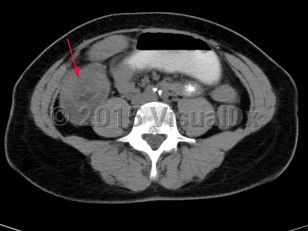

Intussusception is a telescoping or invagination of a part of the intestine into the lumen of an adjacent segment. Intussusception can present with variable severity. It can present with bowel ischemia and perforation with need for emergent surgical intervention, or it can present as relaxing / remitting abdominal pain of unclear etiology with intermittent symptoms and no signs of systemic illness. Jejunojejunal, jejunoileal, ileoileal, ileocolonic, and colocolonic are all types of intussusception that can occur, with the majority involving the small intestine.

Intussusception in adults presents with similar symptoms: sudden-onset abdominal pain that can relax and remit, with or without symptoms of acute bowel obstruction and hematochezia. Intussusception in adults can also be caused by viral infections, polyps, or postsurgical adhesions, but there is greater concern for underlying malignancy – either small or large bowel or extrinsic (eg, lymphoma) – as a trigger point.

Initial management requires ensuring hemodynamic stability, as many patients are dehydrated, and assessing concern for bowel perforation, which could require broad-spectrum antibiotics and urgent surgical intervention. Air or barium enemas can be both diagnostic and therapeutic. However, intussusception will frequently recur, in which case surgical resection is often required. Further imaging (ie, small bowel x-ray series, CT or MRI abdomen) can be utilized to identify the etiology if it is unknown based on presenting symptoms and a barium / air enema.